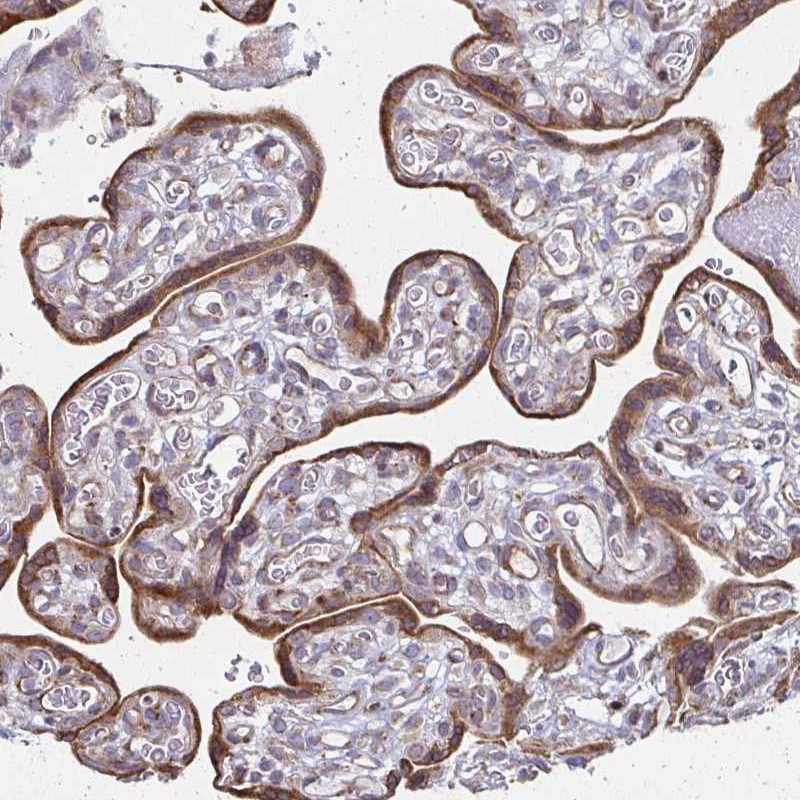

Immunohistochemical staining of human placenta shows distinct cytoplasmic positivity in trophoblastic cells.